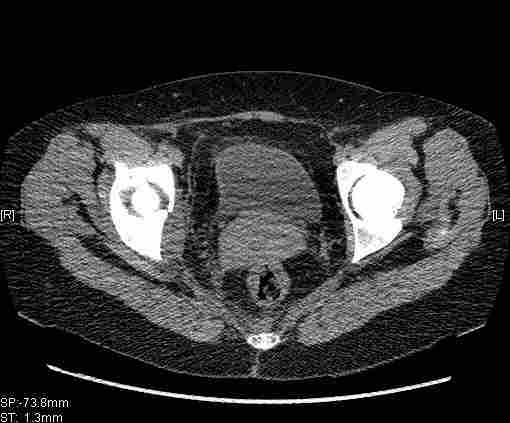

Женщина,58 лет, после ДТП 6 суток. Первично повреждение расценено как переломы ветвей лонной кости. После подтверждения повреждения вертлужной впадины,как чаще всего случается, вопрос встал о тактике. БОльшинство за консерватиное лечение.К сожалению кт у нас "во время" сломался. Прилагаю стандартные снимки вертлужки. У меня следующие вопросы к коллегам:1. Правильно ли рассценивать это повреждение как Т-образный перелом вертлужнй впадины?2. Можно ли добиться анатомической репозиции поверхности вертлужной впадины скелетным вытяжением в данном случае, если нет, что будет этому препятствовать?3. Если смещение останется таким как сейчас, через какое время появится необходимость эндопротезирования (по вашему опыту)?Спасибо.

Удалось сегодня вывести пациентку в соседнюю больницу, где есть кт. Срезы сделаны только горизонтальные.

Приветствую,Антон.Рункова рядом нет,но после полученных данных КТ,обсуждали совместно.Итог обсуждения-развернутый ответ дать не получится,т.к.срезы выбраны не информативные.Если ориентироваться на данные 3D,то ,ИМХО,можно лечить на вытяжении.

Спасибо, Салават и коллеги. Насколько я понял,нужны срезы в сагитальной и фронтальной плоскостях?